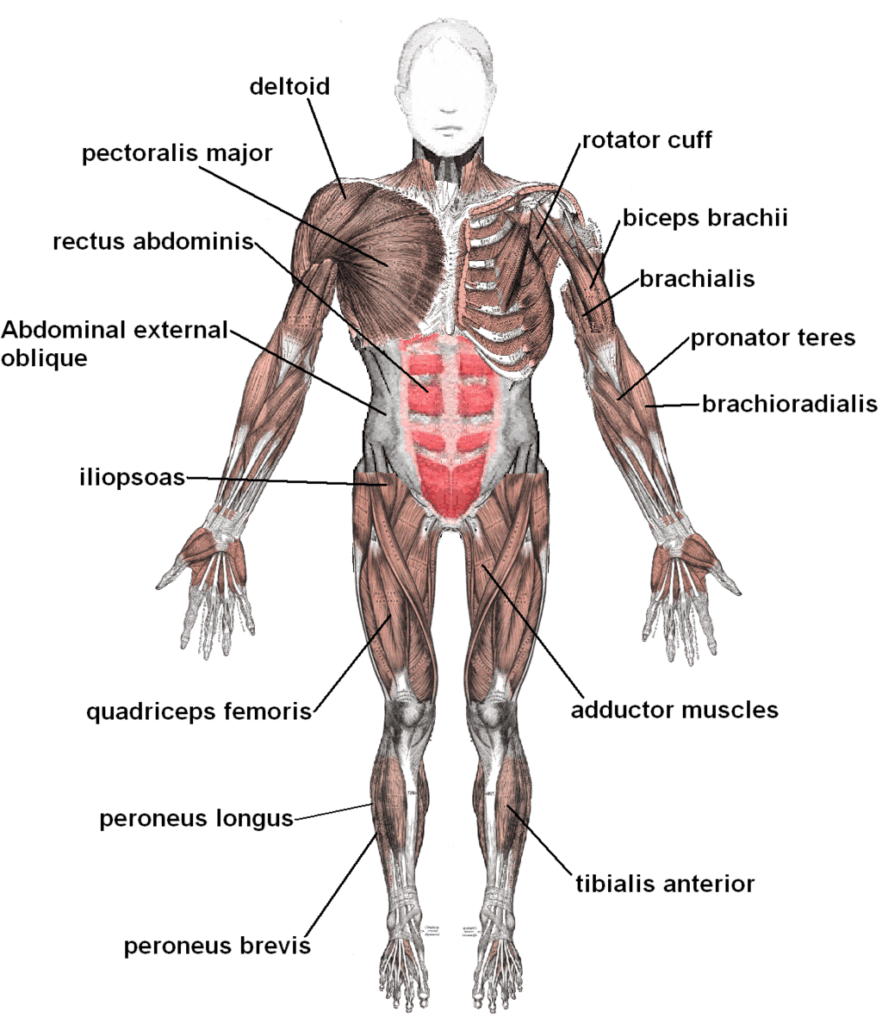

The function of muscles is to tolerate movement of the body. They are made up of small bundles of fascicles or muscle fibers. Fascicles, in turn, are made up of single muscle fibers that are connected to each other in a special way that gives them the capacity to slide simultaneously. The reason why is that muscles can be slid apart, shortened, and permit the muscles to increase in length. Muscles move in harmony with bones with the help of tendons which enable the muscles to attach with the bones. The shifting of the muscles to the tendons happens slowly as tendon fibers give way to muscle fibers prior to the bone attachment. Tendons may vary from short to long depending on their location in the body. The muscles can shorten and pull the tendons as the muscles contract.

A torn muscle is an injury triggered by an overstretched tendon or muscle. The bundle of fiber is torn apart and loses its ability to contract. The amount of tissue damage is the basis for the severity of the injury. The most frequent cause of this condition is overuse of muscles that eventually weaken them. If the joints and muscles perform an activity which they are not designed or prepared to do, an injury can come about from one stressful event, or it may progress slowly after many habitual motions. The damage can be graded on its severity in three areas, such as: the intersection of muscle and tendon, the muscle itself, and the tendon itself.

Pulled muscles are injuries that are caused by damaged ligaments. Ligaments are the thick group of tissues that stabilize and surround joints. This ligament allows the joints to be in motion only on limited directions. A number of joints move about in various planes which, therefore, require more than a group of ligaments to grasp the joint in its proper location and alignment. On each side of the joint, the ligaments are connected to the bone. If a ligament is stretched, then the damage is called a sprain.

The most common location for pulled muscles is the ankles. The mechanism of damage is abruptly twisting or rolling the ankle and rotating it internally so that the foot’s sole starts to point up. This causes damage and stretches the ligaments on the outer part of the ankle. Muscle strains or tears may include any body part that is used to execute work. Back pain in the lower region and spasm is an outcome of frequent lifting injuries.